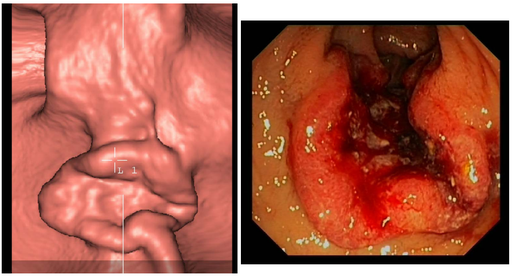

Cancers colo-rectaux

DANSE E. - UCL

Digestif MASTER 1

Contraste digestif en radiologie adulte